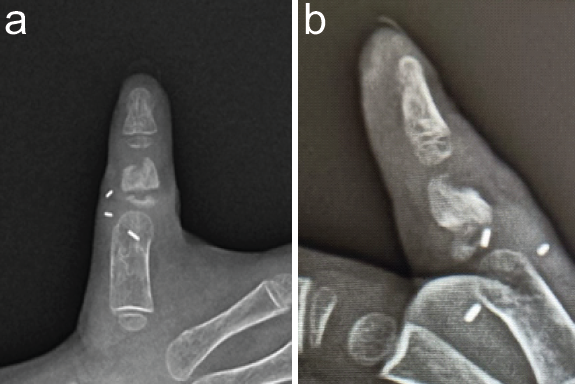

Post-operative radiographs verified satisfactory bone alignment and K-wire positioning (Fig. 4a and 4b).

Figure 4: (a) Post-operative X-ray anteroposterior view. (b) Post-operative X-ray lateral view.